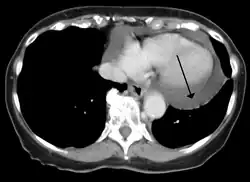

Cardiac CT and MRI scans: cross-sectional imaging with computed tomography (CT) can help localize and quantify the effusion, especially in a loculated effusion (an effusion contained to one area).[12] CT imaging also helps assess for pericardial pathology (pericardial thickening, constrictive pericarditis, malignancy-associated pericarditis).[1] Whereas cardiac MRI is reserved for patients with poor echocardiogram findings and for assessing pericardial inflammation, especially for patients with continued inflammation despite treatment.[5] CT and MRI imaging can also be used for continued follow up on patients.